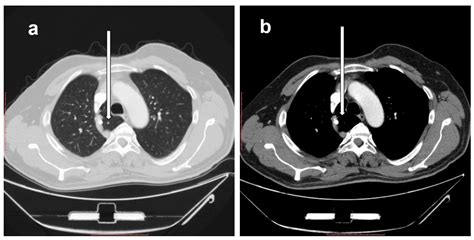

The hallmark of the Vena Azygos Lobe on a chest radiograph is a characteristic curvilinear density. Because of its unique formation, it is easily identifiable if one knows what to look for. Clinicians and radiologists typically identify the following features:

• The Azygos Fissure Line: A thin, convex line extending from the apex of the right lung toward the hilum.

• The Azygos Point (or Teardrop): A dense, teardrop-shaped opacity at the inferior end of the fissure line. This represents the cross-section of the misplaced azygos vein itself.

• Location: Always found in the right upper lobe.

While standard chest X-rays are usually sufficient for diagnosis, computed tomography (CT) provides a definitive view. On a CT scan, the Vena Azygos Lobe is clearly demonstrated as an isolated pleural-lined segment of lung tissue separated from the rest of the right upper lobe by the azygos fissure.